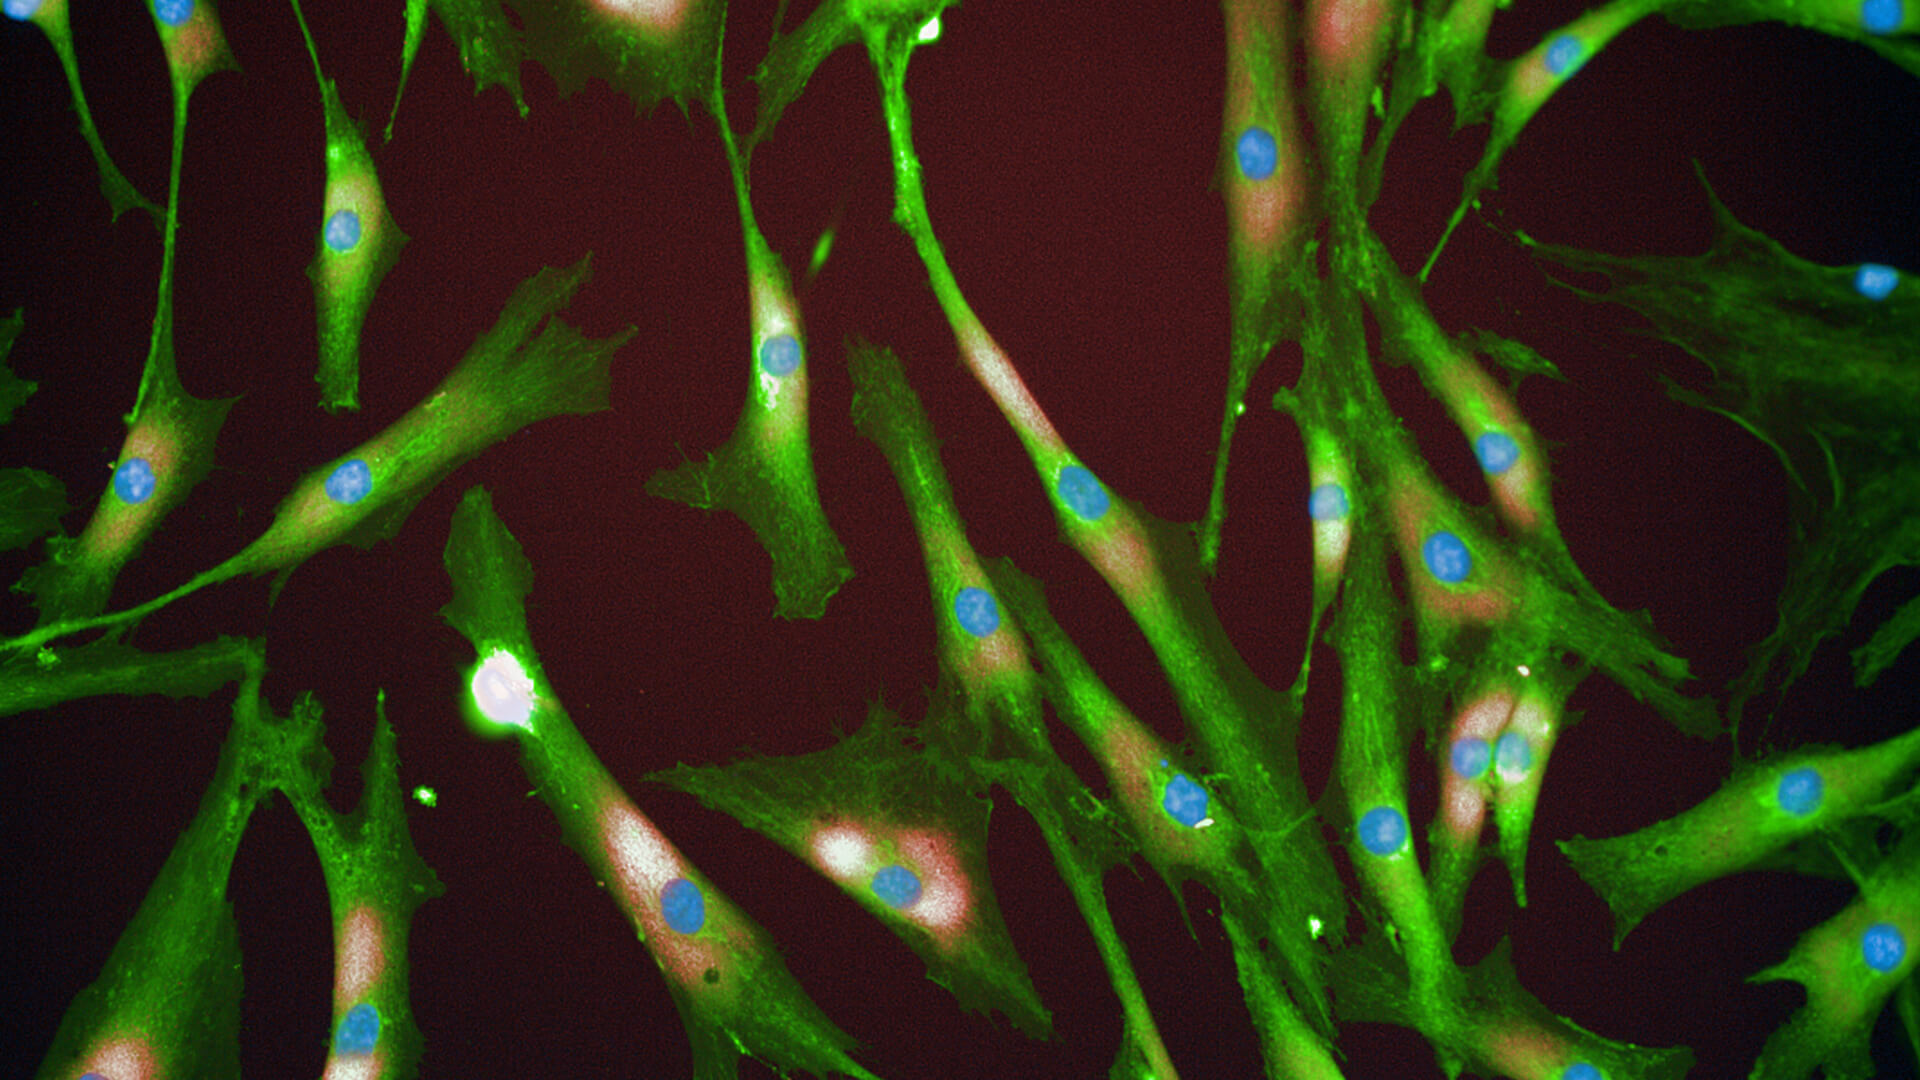

Rejuvenated Senescent Fibroblasts.

Rejuvenated Senescent Fibroblasts.